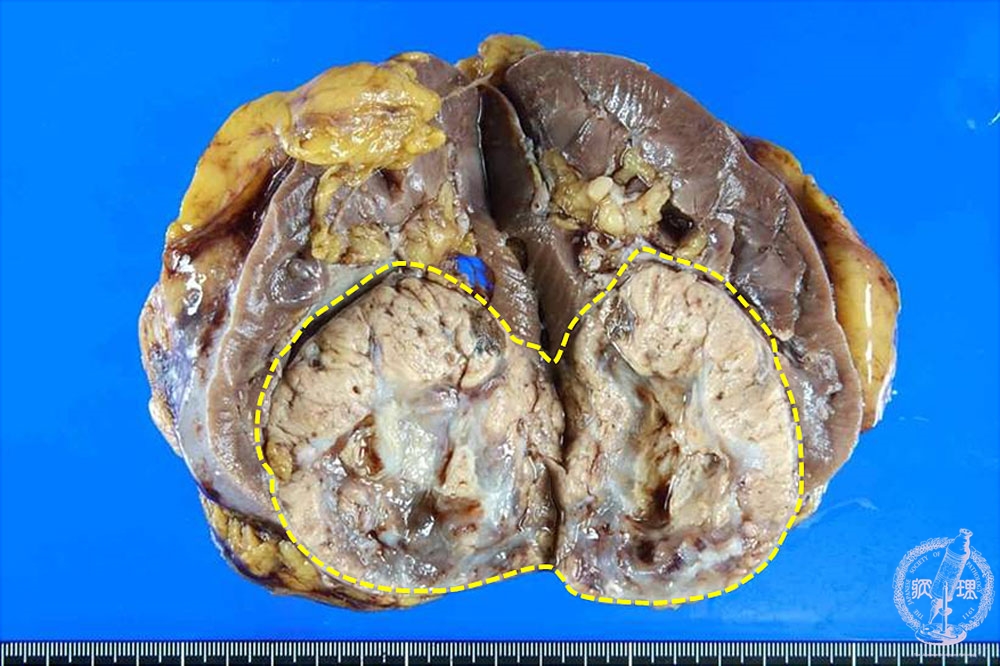

腎血管平滑筋脂肪腫(結節性硬化症)マクロ像

マクロ像:黄色調が主体の境界明瞭な腫瘤が認められる。結節性硬化症に合併することが多い。